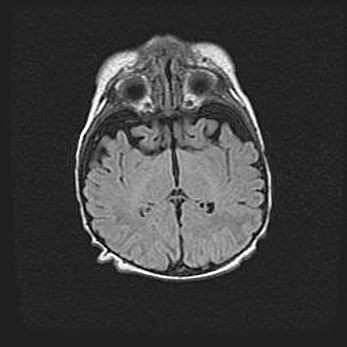

Множественные кисты обоих полушарий головного мозга, наибольшая из них в правой затылочной области. Ассиметричная атрофическая гидроцефалия.

Возраст: 7 месяцев

Вес: 5660 г

Пол: мужской

Окружность головы: 41,5 см

Срок гестации: 28-29 недель

Кисты головного мозга развиваются в результате многоочаговых некрозов вещества мозга и возникают вследствие перенесенной перинатальной инфекции, менингитов, энцефалитов, асфиксии, родовой травмы, расстройств мозгового кровообращения различного генеза. Образованию кист в веществе головного мозга плодов и новорожденных способствуют такие факторы, как высокое содержание в нем воды, недостаточная (или отсутствие) миелинизация и слабая астроглиальная реакция на повреждение.

Кисты могут сочетаться с гидроцефалией и другими поражениями головного мозга.